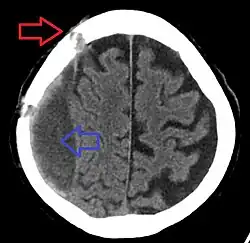

A person must receive medical assessment, including a complete neurological examination, after any head trauma. A CT scan or MRI scan will usually detect significant subdural hematomas.

Subdural hematomas occur most often around the tops and sides of the frontal and parietal lobes.[3][2] They also occur in the posterior cranial fossa, and near the falx cerebri and tentorium cerebelli.[3] Unlike epidural hematomas, which cannot expand past the sutures of the skull, subdural hematomas can expand along the inside of the skull, creating a concave shape that follows the curve of the brain, stopping only at dural reflections like the tentorium cerebelli and falx cerebri.

On a CT scan, subdural hematomas are classically crescent-shaped, with a concave surface away from the skull. However, they can have a convex appearance, especially in the early stages of bleeding. This may cause difficulty in distinguishing between subdural and epidural hemorrhages. A more reliable indicator of subdural hemorrhage is its involvement of a larger portion of the cerebral hemisphere. Subdural blood can also be seen as a layering density along the tentorium cerebelli. This can be a chronic, stable process, since the feeding system is low-pressure. In such cases, subtle signs of bleeding—such as effacement of sulci or medial displacement of the junction between gray matter and white matter—may be apparent.

Fresh subdural bleeding is hyperdense, but becomes more hypodense over time due to dissolution of cellular elements. After 3–14 days, the bleeding becomes isodense with brain tissue and may therefore be missed.[20] Subsequently, it will become more hypodense than brain tissue.[21]